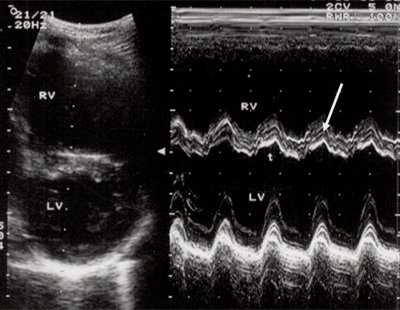

Характерными особенностями выраженной объемной перегрузки правого желудочка являются дилатация желудочка, при которой толщина миокарда не превышает верхней границы нормы, увеличение правого предсердия, парадоксальный характер движения межжелудочковой перегородки и увеличение амплитуды движения трикуспидального клапана (рис. 2, 3).

Рис. 3. Объемная перегрузка правого желудочка при дефекте межпредсердной перегородки. В- и М-сканирование. Стрелкой показан парадоксальный характер движения межжелудочковой перегородки.

IVS - межжелудочковая перегородка, MLV - миокард левого желудочка, LV и RV - левый и правый желудочек.